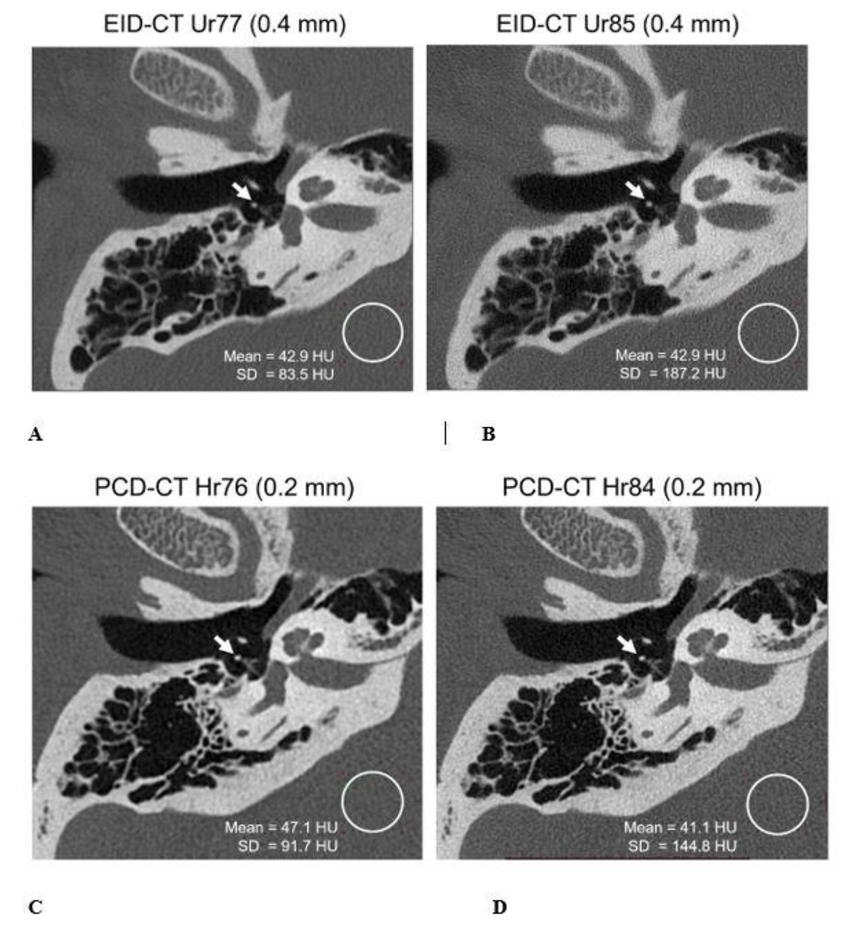

Figure 6. A 72-year-old male scanned on energy-integrating detector (EID) CT and photon-counting detector (PCD) CT for temporal bone examination. Right temporal bone images (oblique axial plane) from EID-CT were reconstructed using ultra-high-resolution-regular (Ur) kernels - Ur77 and Ur85 at 0.4-mm section thickness and PCD-CT using head-regular (Hr) kernels - Hr76 and Hr84 at 0.2-mm section thickness. PCD-CT show better trabecular detail and delineation of the stapes compared to EID-CT (images A/B versus C/D), despite use of 30% (46.4 versus 32.6 mGy) lower dose for PCD-CT. Display window/level = 3800/700 HU. SD: standard deviation of pixel values in the region-of-interest.